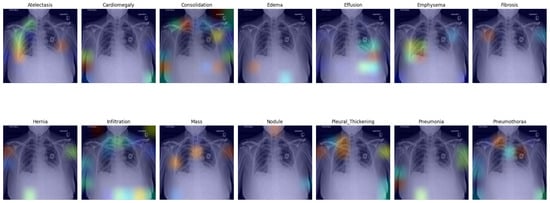

3.5. Visual Representation

In this section, we present a visual interpretation of the learned features, using the Gradient-weighted Class Activation Mapping technique (Grad-CAM) [33]. Grad-CAM offers a technique to produce “visual explanations” for decisions from a broad array of CNN-based models, enhancing their transparency and interpretability. Grad-CAM utilizes the gradients of any target concept (e.g., ‘Effusion’ in the current context) flowing into the final convolutional layer to generate a coarse localization map. This map highlights the crucial regions in the image for predicting the concept [33]. Unlike prior methods, Grad-CAM can be applied to various CNN architectures without the need for re-training or architectural modifications.

Figure 4 presents the default classifier head. In the first picture in the first row, atelectasis was mistaken due to overlapping rib arches. Since the left hemidiaphragm was obscured by the enlarged cardiac shadow, effusion in the fifth image in the first row is marked below the expected level of the diaphragm (blue). In the sixth image in the first row, emphysema was suggested, probably due to the significant difference in the overall density of the lung bases. In the third picture in the second row, the enlarged aortic knob was mistaken for a mass. In the seventh picture in the second row, pneumothorax was suggested in the right apex. This area is often difficult to assess for junior radiologists; as the bronchovascular pattern is faint, it can raise a false suspicion of pneumothorax.

Figure 4. Grad-CAM of model with the default classifer.